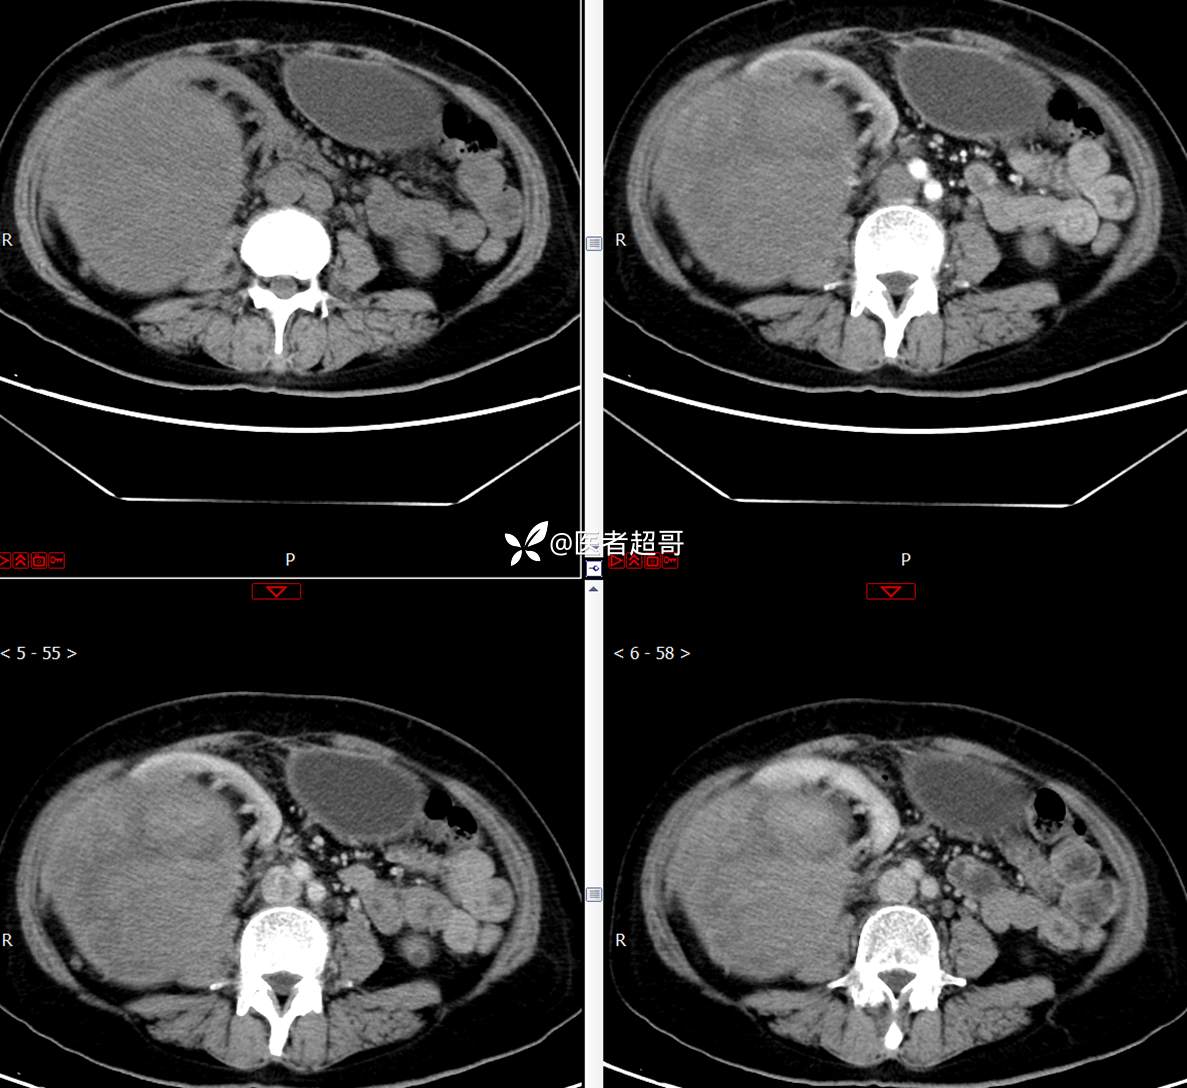

现病史:患者1周余前发现右上腹有一半球形巨大肿物,约18cm*15cm大小,既往贫血病史3年余,诉乏力,易疲劳,偶有头晕,活动后心悸,无腹痛、腹胀,无恶心、呕吐,无尿频、尿急、尿痛,无排尿困难,患者为求进一步治疗,来我院消化内科就诊,门诊行肝.胆.胰.脾.肾彩超示:右肾上部囊实性占位,范围约18.0cm×11.7cm×16.4cm,边界清,形态规则,建议进一步检查,腹膜后实性结节。我科遂以“肾肿物”收治入院,患者自发病以来,神志清、精神可,睡眠、饮食可,二便正常,体重、体力略有下降。